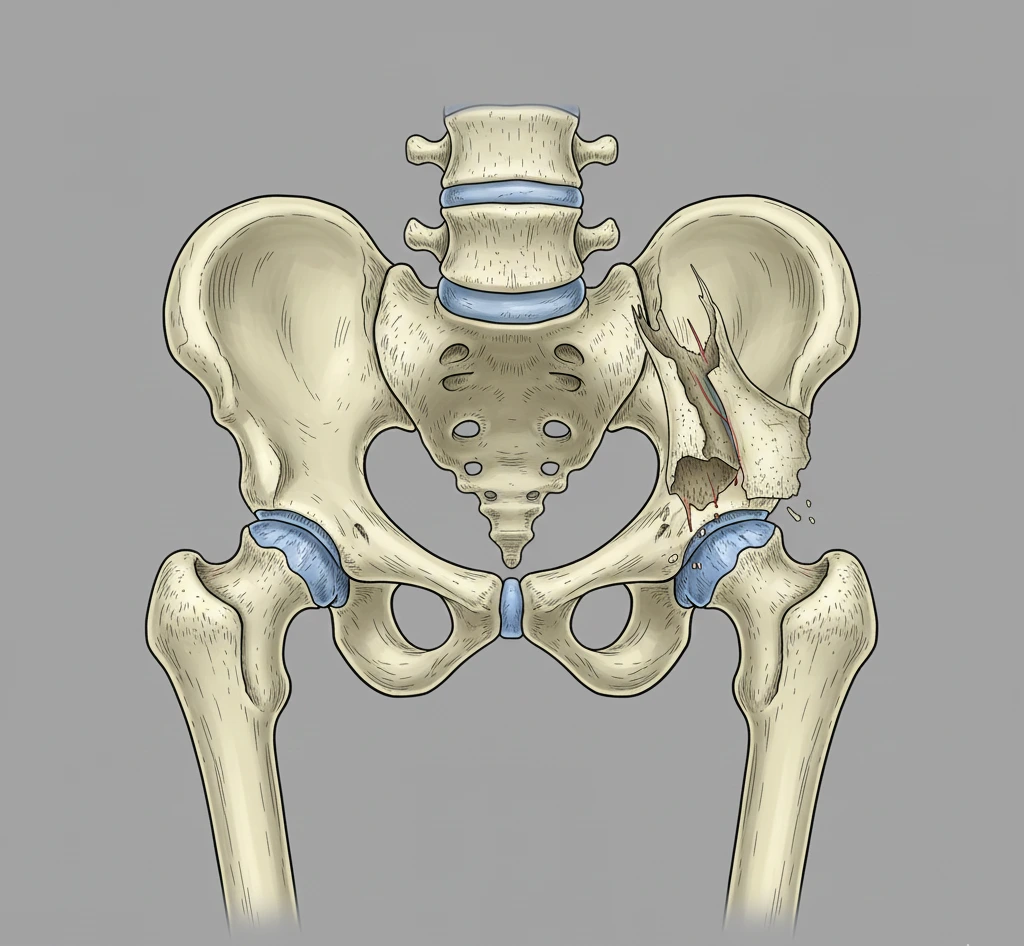

Важливість реабілітації після перелому шийки стегна

Перелом шийки стегна є однією з найпоширеніших травм, особливо серед людей похилого віку, тому відновлення після такої травми – тривалий процес, що вимагає комплексного підходу. Правильна реабілітація після перелому шийки стегна допомагає повернути рухливість, зміцнити м’язи та запобігти ускладненням.